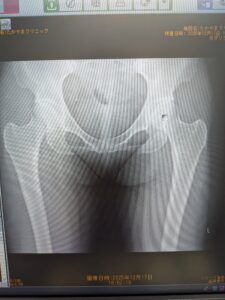

当院放射線科の特徴は、単純XP撮影での撮影・骨密度検査・超音波検査(エコー)などの画像診断を担当しています。撮影・検査後の画像や読影診断レポートを電子カルテと共有し、迅速な治療方針の決定に大きく貢献しています。骨密度検査は精度の高い骨密度測定器を導入しています。また、超音波検査(エコー)は、頸動脈(動脈硬化)・甲状腺・腹部等の検査を行っています。検査をご希望の方は、お電話でご連絡いただくか、お気軽にスタッフにお尋ねください。